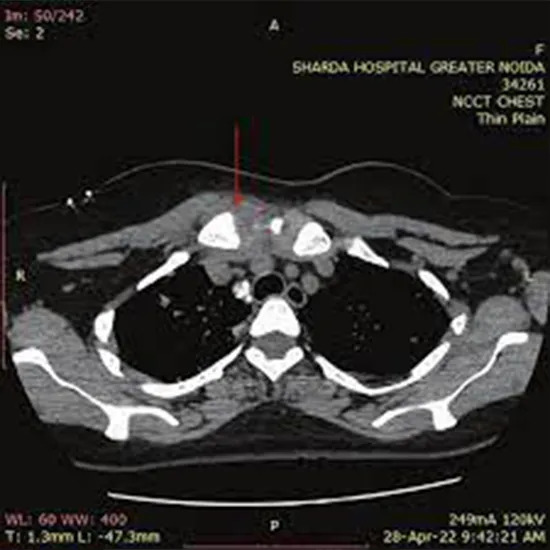

An NCCT Sternoclavicular (Non-Contrast CT Scan) is a special scanning method that takes clear pictures of the sternoclavicular joint, which connects the breastbone (sternum) and the collarbone (clavicle). Unlike CECT, this scan does not use contrast dye, making it a non-invasive option for diagnosing sternoclavicular joint problems. An NCCT Sternoclavicular scan identifies issues like dislocations in joints, fractures, tumors, or swelling in the sternoclavicular joint. The scan provides clear images, showing important information when regular imaging methods, like X-rays, do not provide enough detail.